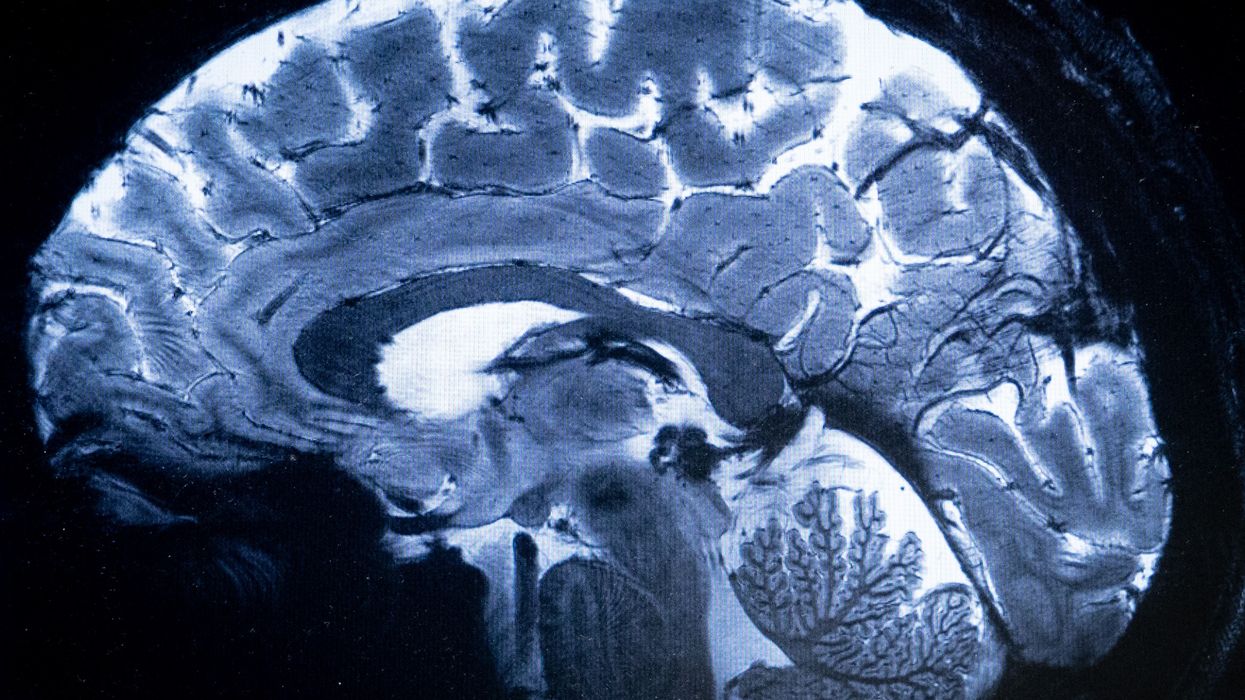

The research team studied the exposure of close to 2,700 preteens to monthly temperatures from birth until they turned eight years old. They used magnetic resonance imaging (MRI) brain scans.

The impacts of the exposure were measured between nine-12 years of age. For this, the researchers assessed the preteens' white matter connectivity by measuring how water flowed and spread in their brains, or 'mean diffusivity'.

In more mature brains, water flows more in one direction than in all directions, showing lower mean diffusivity, the study said. The team found that exposure to colder-than-usual temperatures during pregnancy and the first year of life, and exposure to hotter-than-usual environments from birth until three years of age were linked with more mean diffusivity at preadolescence, pointing to a slower maturation of their white matter.

"The fibres of the white matter are responsible for connecting the different areas of the brain, enabling communication between them. As the white matter develops, this communication becomes faster and more efficient," said first author Laura Granés, a researcher at ISGlobal. "Our study is like a photograph at a particular moment in time and what we see in that image is that participants more exposed to cold and heat show differences in a parameter -- the mean diffusivity -- which is related to a lower level of maturation of the white matter," said Granes.